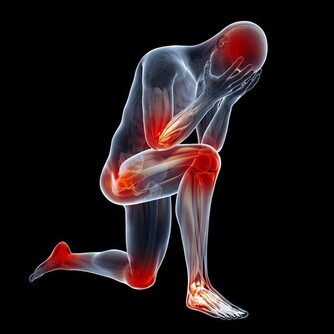

無論哪一種舉手療法,時間一長就會很難受,並有痠痛麻脹之苦。

然而此功的奇妙之處,正在於它的痠痛麻脹,痠痛麻脹所顯示的即是身體氣血阻塞的現象。

為了要持久舉手,手臂必須調動很多氣血來支應,

在調動氣血的過程中,凡有阻塞之處必然引起痠痛麻脹。

只要忍受痠痛麻脹到一定的時間,痠痛麻脹的現像一定會解除,這表示阻塞已被打通。